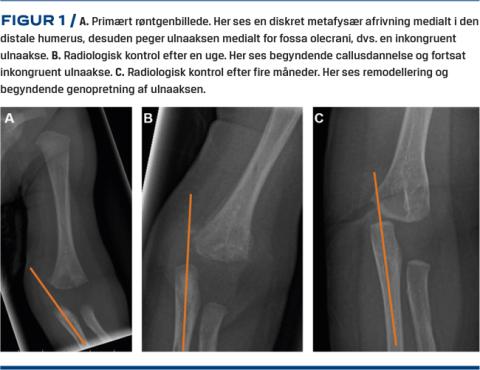

Et spædbarn blev behandlet på en børneafdeling en uge efter forløsning ved kejsersnit, idet venstre arm ikke kunne bevæges. Der blev taget et røntgenbillede af overarmen og albuen, og radiologisk kunne der beskrives en diskret metafysær afrivning medialt i den distale humerus (Figur 1). Barnet fik derfor anlagt en vinkelgipsskinne og blev set til kontrol på en ortopædkirurgisk afdeling en uge senere. I mellemtiden blev der foretaget underretning på mistanke om BCS. Ved den ambulante røntgenkontrol efter en uge, fandt man en komplet disloceret epifysiolyse i den distale humerus (EDH) (Figur 1B). Man fortsatte med gipsbehandlingen i yderligere to uger. Ved den afsluttende kontrol fire måneder postoperativt var der nærnormal bevægelighed i albuen med radiologisk remodellering (Figur 1).

Forbeningskernerne omkring albuen begynder først at blive synlige fra etårsalderen. Det er derfor vigtigt at være opmærksom på akserne og den manglende ossifikation af epifyserne omkring albuen for at erkende epifysiolyser, luksationer og frakturer. Hos barnet i sygehistorien sås der malalignment af ulna i forhold til humerus (Figur 1). Ved en sådan opdagelse bør der rejses mistanke om komplet epifysiolyse eller luksation, idet ulna er en lige knogle, som er placeret i forlængelse af fossa olecrani. Albueluksation hos nyfødte sker dog ekstremt sjældent, hvorfor man primært må have mistanke om EDH. Epifysiolyse er ofte karakteriseret ved posteromedial malalignment modsat luksation, som er forskudt posterolateralt. Luksation i albueleddet kræver reponering af leddet og immobilisering i en vinkelgipsskinne. Omvendt er der ingen entydig evidens for kirurgisk intervention ved behandling af EDH [3]. Diagnosen kan stilles ved regelrette røntgenbilleder af den distale humerus for at tydeliggøre visualiseringen af akserne omkring albuen. Her bør man være opmærksom på den manglende ossifikation, og ulnaaksen skal dermed pege imod fossa olecrani. Ved fortsat tvivl kan diagnosen stilles endeligt ved UL -eller MR-skanning [4]. Brugen af UL-skanning til diagnosticering af EDH kan være gavnlig, om end undersøgelsen er meget behandlerafhængig. Ydermere bidrager EDH’s sjældne forekomst til at limitere erfaringen i radiologisk regi, hvilket kan begrænse brugen af UL-skanning lokalt. Da en MR-skanning ofte kræver, at barnet lægges i generel anæstesi, kan man overveje artrografi som alternativ. Her er barnet også fuldt bedøvet, men til gengæld vil man sikkert kunne skelne mellem en luksation og en EDH. Samtidig vil man nemt kunne ophæve en evt. luksation og bandagere barnet i en vinkelgipsskinne med underarmen i pronation eller foretage k-trådsfiksation efter reposition ved EDH, hvis det findes indiceret [5]. Det bør dog understreges, at det kan være vanskeligt at udføre en artrografi hos spædbørn, hvorfor man bør holde sig til MR-skanning som supplement til røntgenoptagelse for at stille diagnosen, hvis erfaringen med artrografi er beskeden. CT har ingen plads i diagnosticeringen af EDH pga. både manglende ossifikation i albuen og strålingsbyrden.